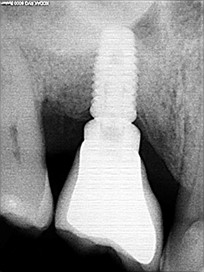

Une greffe osseuse d’apposition est une technique de chirurgie pré implantaire indiquée lorsque le patient a une largeur osseuse (maxillaire ou mandibule) insuffisante rapportée au diamètre de l’implant, soit car le diamètre de l’implant est trop important, soit car la pose de l’implant nécessite un remodelage osseux.

Ce type de greffe osseuse traite donc les déficits osseux dits horizontaux. La technique est relativement simple, sous anesthésie générale ou locale.

Il effectue une incision dans la gencive : il repousse les tissus mous et une fois qu’il a accès à l’os, Selon leur taille, il faut parfois les fixer avec une vis d’ostéosynthèse (pour les greffes d’apposition, il faut toujours mettre une ou plusieurs vis). Une fois la greffe effectuée, le praticien la recouvre parfois d’une membrane type collagène qui isole le greffon de la gencive, pour bien permettre la greffe sur l’os.

La consolidation optimale d’une greffe osseuse nécessite plusieurs mois. Des techniques d’imagerie médicale type cone-beam permettent de bien objectiver la réussite de cette consolidation de la greffe osseuse dentaire.